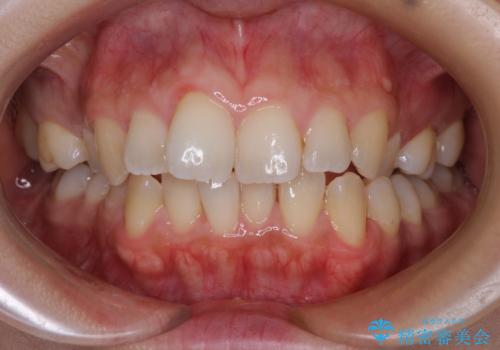

前歯のデコボコを改善 インビザラインの矯正治療

- 前歯のデコボコを治したいとのことで来院された患者様です。

上下顎ともに歯列全体の後方移動とIPR(歯と歯の間を削る)によってデコボコが解消するように設計し、インビザラインにより治療を行うこととしました。